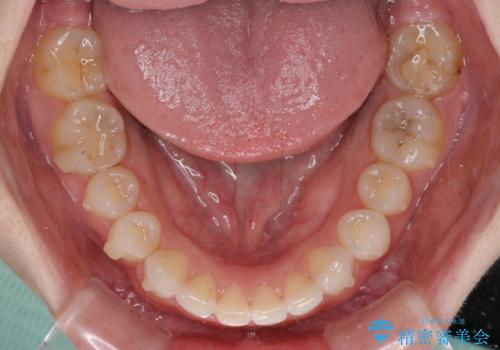

治療前、下顎前歯はほとんど見えない咬み合わせでしたが、矯正治療によりディープバイトが改善されました。